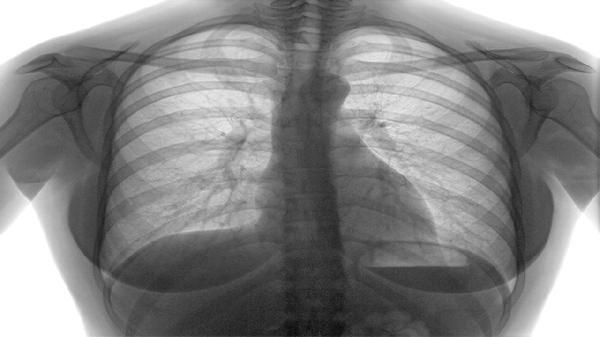

慢阻肺病人如何排痰 这几个促排痰方法详述

慢阻肺病人可通过体位引流、有效咳嗽训练、雾化吸入治疗、胸部叩击排痰、药物祛痰等方式促进排痰。慢阻肺即慢性阻塞性肺疾病,患者因气道黏液分泌增多且清除能力下降,易出现痰液潴留。